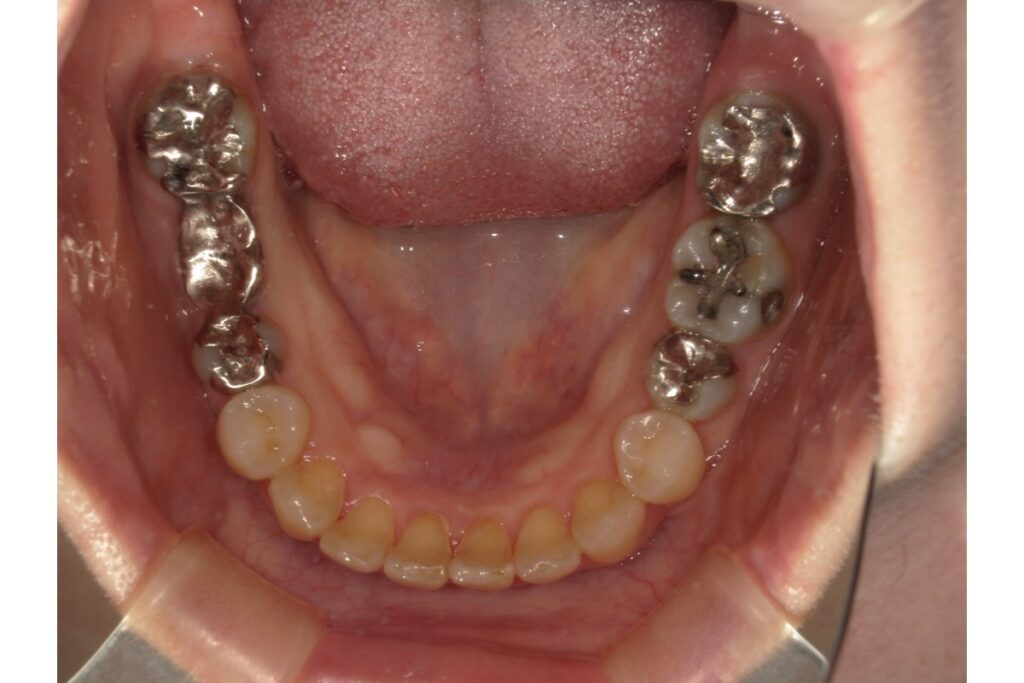

5.症例紹介

実際に補綴物の入っている治療の症例をご紹介します、インビザラインにて治療されました。

治療期間は約1年です。